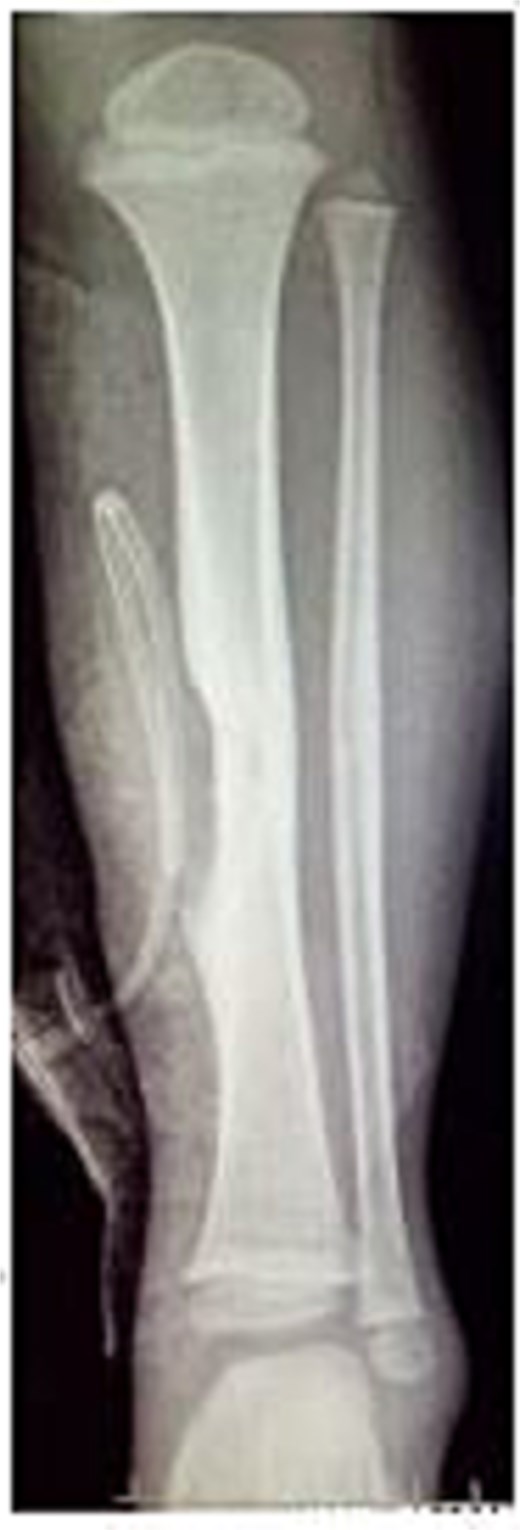

A 4-year-old boy presented with swelling on the medial aspect of his left leg. Three months prior, the patient had sustained a left tibial shaft fracture, initially treated conservatively. The swelling developed gradually with localized tenderness. On examination, the swelling was firm and tender to palpation, with intact overlying skin (Fig. 1). Radiography revealed erosion of the tibia (Fig. 2). Given the patient's fracture history, the initial differential included osteomyelitis, and empirical antibiotics were started. The vascular surgery team suspected a pseudoaneurysm and recommended further evaluation. Doppler ultrasound confirmed a pseudoaneurysm, revealing an abnormal vascular structure with turbulent blood flow. To delineate the vascular anatomy and identify the pseudoaneurysm's origin, magnetic resonance angiography (MRA) was ordered. It demonstrated the pseudoaneurysm arising from an unnamed posterior tibial artery branch, likely injured during initial trauma. The aneurysmal sac was located near the fracture site, eroding the underlying tibial bone (Fig. 3). The pseudoaneurysm's size warranted surgical intervention. The patient underwent excision of the aneurysmal sac and vessel wall repair (Fig. 4). Under general anesthesia, the aneurysmal sac was dissected out (Fig. 5), and the posterior tibial artery wall was repaired with lateral sutures. Hemostasis was achieved, and the wound was closed in layers. The patient had an uneventful postoperative recovery.

MRA showing the pseudoaneurysm arising from an unnamed branch of the posterior tibial artery.

Ultrasound is a key diagnostic tool for aneurysms [16]. It is non-invasive, cost-effective, and requires no contrast or sedation in pediatric patients [17]. Ultrasonography can accurately locate posterior tibial artery aneurysms and detect mural thrombi [18]. In our case, Doppler ultrasound confirmed the pseudoaneurysm and helped assess perfusion for perioperative decisions. MRA and computed tomography angiography are alternative imaging options [4, 17]. Our MRA showed the pseudoaneurysm near the fracture site, eroding the tibial bone, originating from a posterior tibial artery branch. Treatment options include arterial repair, graft interposition, ligation, compression, thrombin injection, and endovascular intervention [6]. With no standard protocol for post-traumatic posterior tibial artery pseudoaneurysms, surgical repair is preferred over conservative treatment due to embolization risks [10]. The patient underwent aneurysmal sac excision and vessel wall repair.